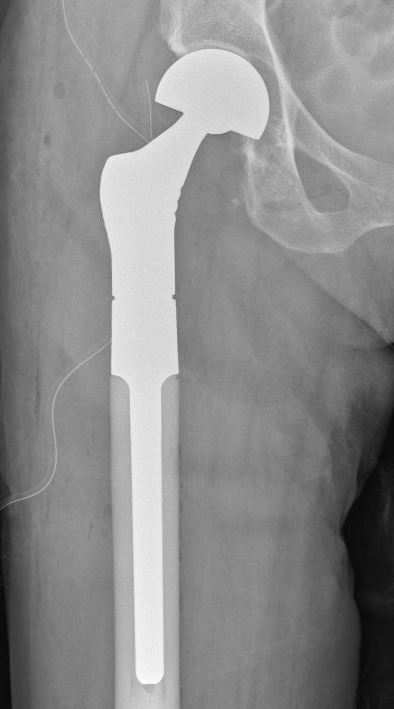

Femoral Neck pathological fracture / Major bone loss

Issues

- fracture unlikely to heal

- hemi versus THA

- long versus short stems

Hemi v THA

Consider life expectancy of patient

Varady et al J Arthroplasty 2019

- hemiarthroplasty versus total hip arthroplasty for pathological femoral neck fractures

- THA longer operative times

- no difference 30 day complication rate

Femoral stem length

- 203 patients with proximal femoral metastasis treated with arthroplasty

- no increased revision rate with short stems

- increased complications with long stems, especially cardiopulmonary complications